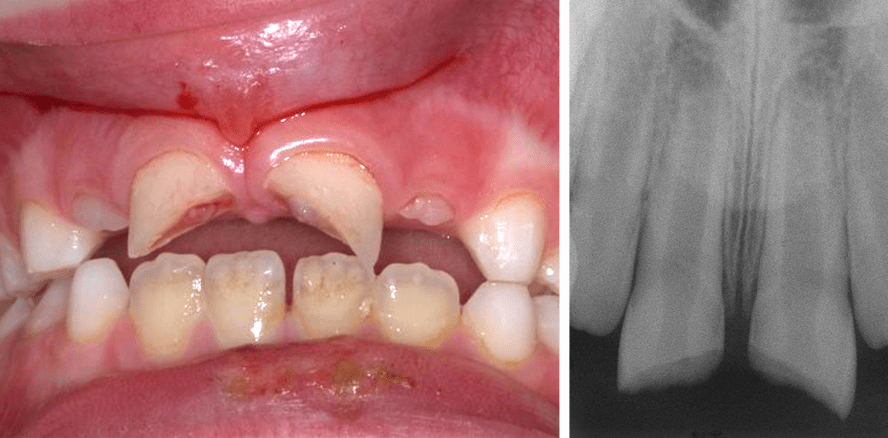

Dislokationsverletzungen treten je nach Richtung und Schwere der Krafteinwirkung in unterschiedlichem Ausmaß und unterschiedlicher Auswirkung auf. Dabei betrifft die Schädigung alle Bestandteile des Zahnhalteapparates.

Die Bedeutung der Nachkontrollen und die Notwendigkeit des interdisziplinären Austausches bei der Behandlung von Traumata soll anhand des nachfolgenden...

Die Bedeutung der Nachkontrollen und die Notwendigkeit des interdisziplinären Austausches...